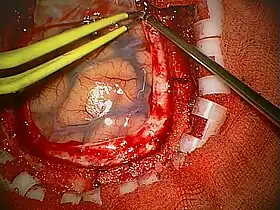

La naturaleza astrocítica de la neoplasia puede resultar bastante fácil de identificar, al menos localmente, en algunos tumores, pero difícil de reconocer en otros, debido al alto grado de anaplasia. La heterogeneidad de región a región del glioblastoma es relevante y dificulta el diagnóstico en muestras limitadas, como las obtenidas por biopsia estereotáxica[69] (véase la fotografía en Cirugía). A pesar de la presencia predominante de células poco diferenciadas, en algunos puntos se pueden distinguir astrocitos neoplásicos más diferenciados. Esto es particularmente cierto en los casos de glioblastoma como resultado de la progresión de un astrocitoma difuso (grado II de la escala OMS). La transición entre zonas que aún poseen diferenciación astrocítica reconocible y zonas de alta anaplasia celular puede ser continua o repentina. Un cambio brusco en la morfología refleja habitualmente la aparición de un tumor diferente, fruto de la adquisición de una o más alteraciones genéticas adicionales.[70]

Cirugía

El abordaje quirúrgico debe elegirse cuidadosamente con el fin de lograr la máxima resección posible del tumor, sin afectar a las estructuras vitales del cerebro y reduciendo al mínimo el riesgo de déficit neurológico posoperatorio.

Los objetivos de la intervención quirúrgica son:

- Obtener un diagnóstico histológico preciso;

- Reducir el efecto masa causado por el tumor y/o el edema peritumoral;

- En su caso, mantener o restablecer el flujo del líquido cefalorraquídeo;

- Conseguir una (potencial) curación a través de la remoción "total" de la neoplasia (en el caso del glioblastoma, es muy raro que la cirugía logre la curación, aun así, puede reducir el tamaño del tumor con el fin de hacerlo más manejable para la radio- y la quimioterapia).

Una resección superior al 98 % del volumen del tumor (resección "total") aumenta la supervivencia en comparación con una resección parcial o subtotal. La resección subtotal "extensa" no parece proporcionar ninguna ventaja de supervivencia en comparación con la biopsia o la resección parcial.[75][82]

A partir de 2006, se demostró la utilidad de utilizar cirugía guiada con fluorescencia de 5-aminolevulínico para mejorar la visualización y el grado de extirpación de estos tumores. Desde esa fecha hasta 2019, se ha generalizado su uso en casi todo el mundo, confirmándose que la tasa de extirpación es superior a la técnica convencional.[83]